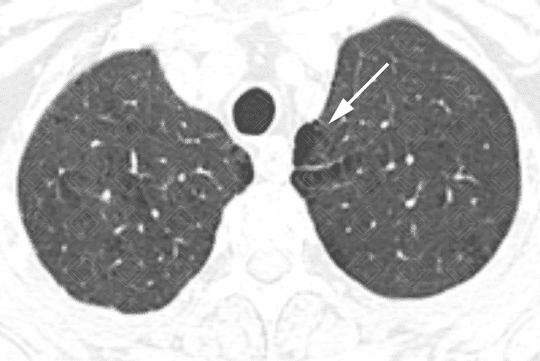

Descrição das figuras 3, 4, 5 e 6: Tomografia computadorizada do tórax seguida de aquisições coronais, sagitais e axiais mostrando as extensas áreas de enfisema centrolobular dispersas pelo parênquima pulmonar (setas vermelhas).

Descrição das figuras 9, 10 e 11: Tomografia computadorizada com aquisições axiais e coronais evidenciando áreas de enfisema parasseptal (seta branca) e centrolobular (setas vermelhas) nos lobos superiores.

• Tomografia computadorizada do tórax: Este método é mais sensível e específico que a radiografia de tórax na avaliação do enfisema. Tem sido empregado para detectar, quantificar e caracterizar a doença. A tomografia é capaz de diferenciar os vários tipos de enfisema, que pode ser classificado, de acordo com a região do ácino acometida, em proximal (centrolobular ou centroacinar - figuras 3, 4, 5, 6, 9, 10 e 11 ), distal (parasseptal - figuras 7, 8, 9, 10 e 11 ) ou todo ácino (panacinar ou panlobular).